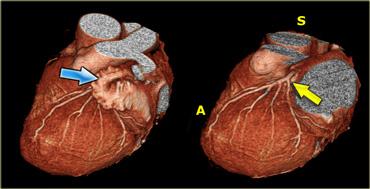

Tái tạo 3D cho thấy tiểu nhĩ trái (mũi tên xanh) và động mạch vành trái (mũi tên vàng) sau khi đã loại bỏ tiểu nhĩ trái. A=trước, S=trên

Khi đánh giá các động mạch vành, cần loại bỏ tiểu nhĩ trái để có thể quan sát được động mạch mũ trái (LCX) và đoạn gần của động mạch liên thất trước (LAD).